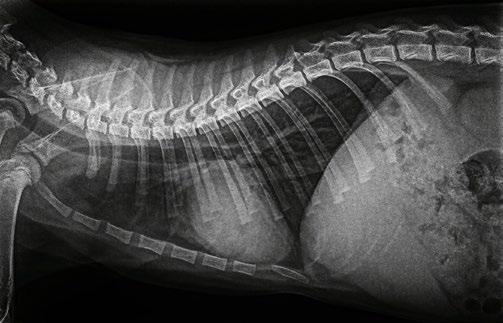

An abdominal ultrasound was performed on Thursday 11th April. The ultrasound showed an area of stomach wall that was thickened up to 2cm in places, with hyperechoic tissue causing loss of stomach wall layering in the region of the thickening. No other abnormalities were seen on ultrasound. Abdominal radiographs were also taken but did not show anything not visible on ultrasound.

2. Ultrasound images showing loss of layering and profound thickening of a portion (stars) of the gastric wall

One month post starting Metalaxyl, PCV is now 28, the dog has gained 1 kg in weight and ultrasound shows visible areas of thickened wall smaller than prior to biopsy. Pearl continues to have episodes of regurgitation and vomiting intermittently, no blood is visible in vomit and faeces have returned to normal colour.

Pearl had a check up on 12.9.2024 and approximately 5 months after starting treatment her weight is now 24.2 kg. Pearl is extremely bright, alert, active and is eating very well. We sedated her to perform ultrasound to assess her progress.

The Ultrasound ( Figures 4) shows there are still some areas with thickening but they are much smaller than previously. I have recommended she stay on medication for another 3 months and then we will repeat the ultrasound.